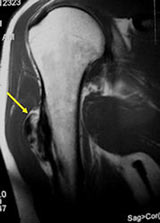

MRI/CT:

- Useful for determining medullary invasion

- Can help discern areas that may be high grade

- Most useful for evaluating the local extent of the tumor and relationship to neurovascular structures the circumference of the femur involved by the tumor (important for surgical planning)

- CT of chest is used for detecting pulmonary metastases